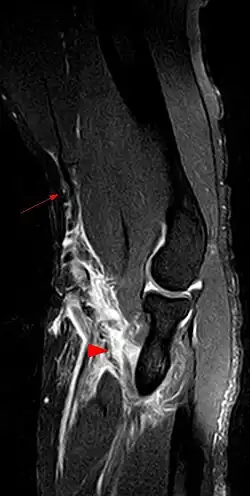

Untersuchungsmethoden

- Anamnese und Klinik im Vergleich zur Gegenseite

- Sonographie

- Röntgen zum Frakturausschluss (proximale Ruptur: Schultergelenk in 2 Ebenen, distale Ruptur: Ellenbogen in 2 Ebenen)[7]

- MRT